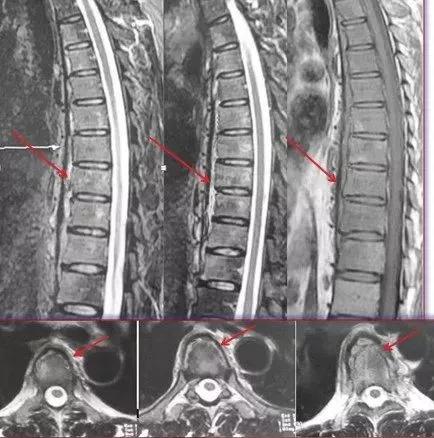

抗结核治疗九个月后,脓肿明显吸收(红色箭头示)。

抗结核治疗十八个月后,脓肿已经完全吸收,病灶愈合(红色箭头示)。脊柱生理曲度良好。